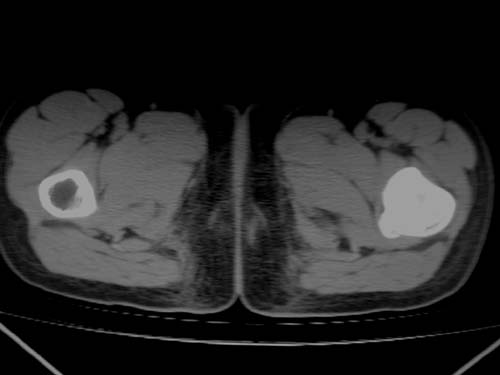

标题: CT19608:女12岁,左髋部疼痛,无发热病史 [打印本页]

标题: CT19608:女12岁,左髋部疼痛,无发热病史

左股骨干增粗,磨玻璃样改变——考虑骨纤维异常增殖症!

考虑左股骨上段骨纤维异常增殖症。

左股骨干增粗,磨玻璃样改变——考虑骨纤维异常增殖症!骨化性纤维瘤?